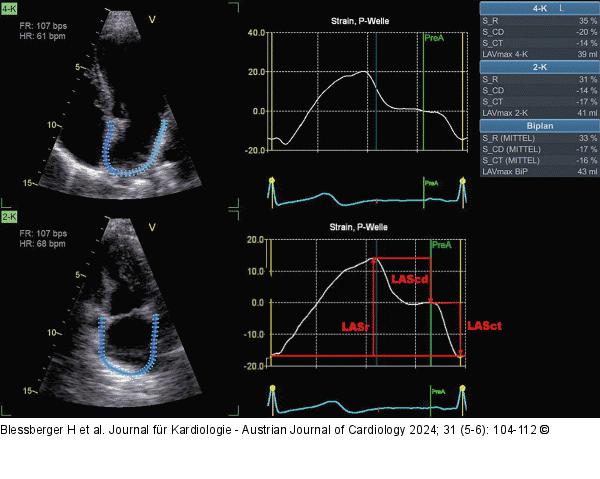

Abbildung 10: Echo Analyse des linksatrialen Strains aus einem apikalen 4-Kammer-Blick (links oben) und einem apikalen 2-Kammer-Blick (links unten). Man beachte die schmale ROI, die dem dünnen atrialen Myokard angepasst ist. In den beiden mittleren Diagrammen sind die linksatrialen Strainkurven mit Annotierung der P-Welle im Oberflächen-EKG abgebildet (P-P-Gating). Die Messwerte in der Tabelle rechtsseitig geben den Reservoir-, Conduit- und Contraction-Strain des linken Vorhofes im 4-Kammer- und 2-Kammer-Blick sowie biplan gemittelt an. LASr: linksatrialer Reservoir-Strain, LAScd: linksatrialer Conduit-Strain, LASct: linksatrialer Contraction-Strain |

Analyse des linksatrialen Strains aus einem apikalen 4-Kammer-Blick (links oben) und einem apikalen 2-Kammer-Blick (links unten). Man beachte die schmale ROI, die dem dünnen atrialen Myokard angepasst ist. In den beiden mittleren Diagrammen sind die linksatrialen Strainkurven mit Annotierung der P-Welle im Oberflächen-EKG abgebildet (P-P-Gating). Die Messwerte in der Tabelle rechtsseitig geben den Reservoir-, Conduit- und Contraction-Strain des linken Vorhofes im 4-Kammer- und 2-Kammer-Blick sowie biplan gemittelt an. LASr: linksatrialer Reservoir-Strain, LAScd: linksatrialer Conduit-Strain, LASct: linksatrialer Contraction-Strain |